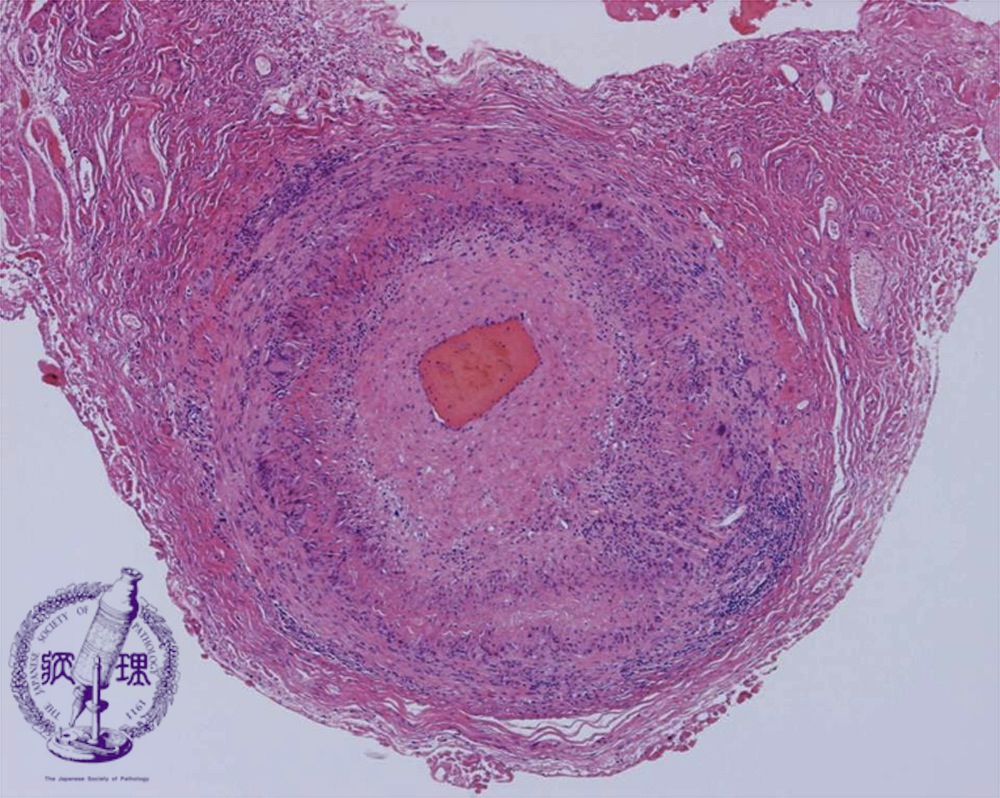

- (14)Giant cell arteritis

Microscopic view (HE, low power view): there is intimal hyperplasia with luminal narrowing.